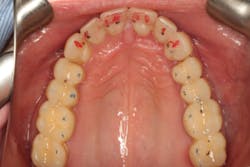

Following the orthodontics, we prepared the maxillary arch for indirect restorations and placed Darren in temporary restorations. We also restored the mandibular incisal edges with direct composites to seal any exposed dentin and refine the incisal plane using a thermoplastic stent fabricated from our diagnostic wax-up. Utilizing a stent to place the direct composites on the incisal edges saved time, and we were able to obtain greater precision in the incisal edge position. Darren was then sent to the periodontist to have the gingival architecture corrected.

Darren remained in the provisionals for three months to allow the soft tissue to fully heal. This also allowed us to evaluate the esthetics, phonetics, occlusion, and function. The importance of provisional restorations cannot be understated, as they provide us with a trial before we place the definitive restorations.

The provisionals were especially important in this case as we had to work out the anterior guidance to be in harmony with the patient's envelope of function. When the provisional restorations were initially placed, Darren continued to feel “locked in” with the position and contours of his canines. Over several appointments, we had to slightly adjust his guidance until he was comfortable while still retaining the function and esthetics.